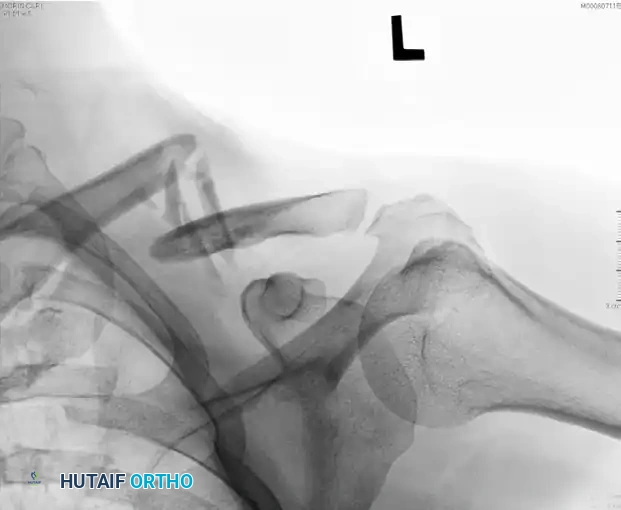

Figure: Preoperative radiograph of a displaced midshaft fracture.

Figure: Preoperative radiograph demonstrating a displaced midshaft clavicular fracture suitable for superior plating.